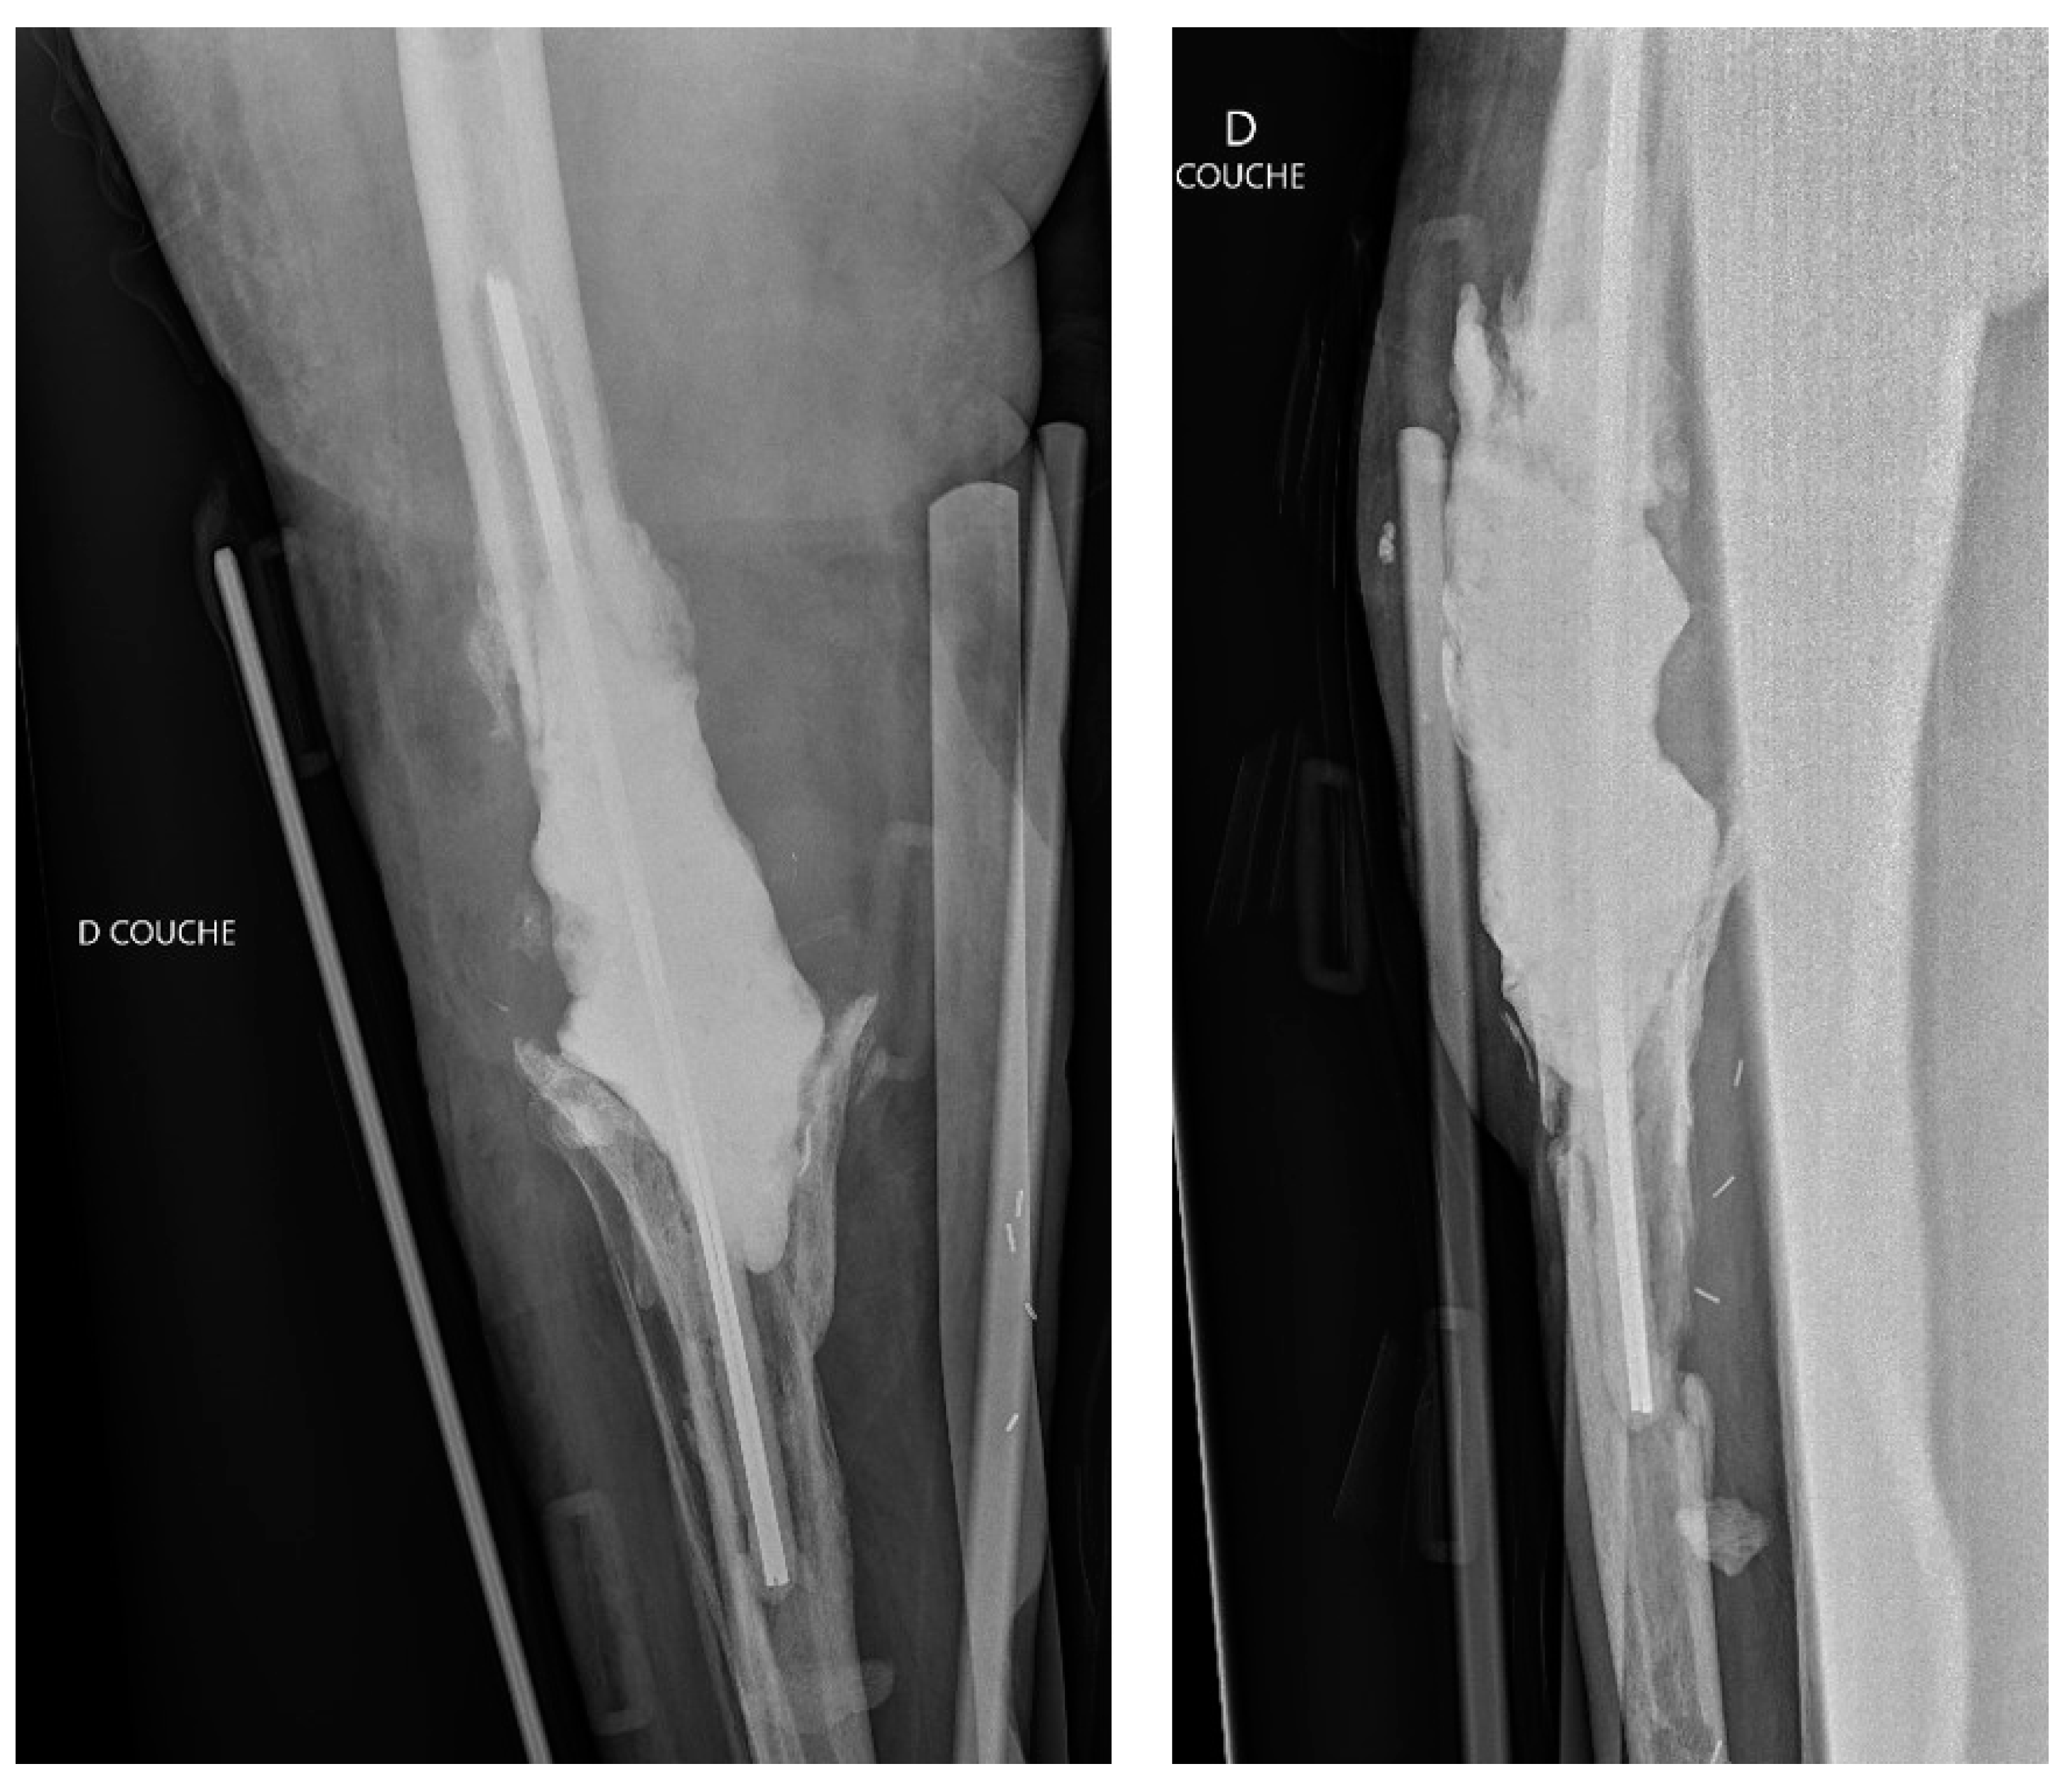

2. Case Presentation